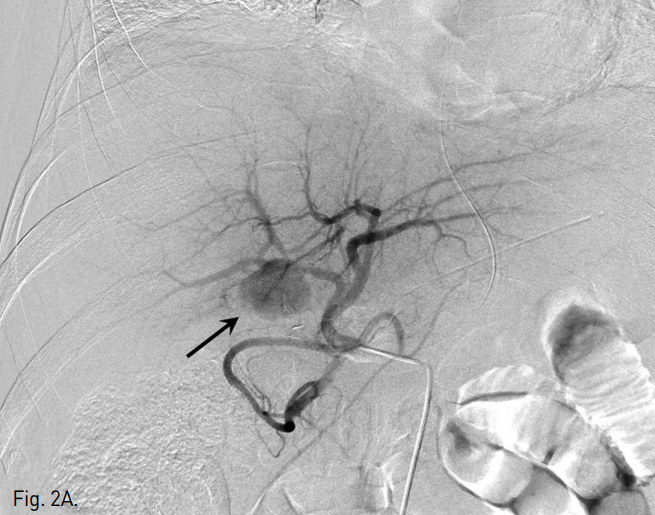

복강동맥조영술에서 우간동맥의 분지부에 인접한 위치에 가성동맥류를 확인하였다(Fig. 2A, B). 6F Shuttle guiding catheter(Cook, Bloomington, IN, USA)로 교체 후에 Stent-graft(4×26mm, JoStent GraftMaster®, JoMed, Germany)를 가성동맥류가 있는 우간동맥에 위치시키고, 풍선카테터(Ultra-thin Diamond,Boston Scientific, Galway, Ireland)를 사용하여 확장시켰다. 시술 직후 시행한 복강동맥조영술에서 동맥류는 관찰되지 않았다(Fig. 2C).

Fig. 2

Celiac (A) and hepatic angiogram (B) show the pseudoaneurysm (arrows in A and B) at distal part of the right hepatic artery near the origin of the right posterior hepatic artery. (C) On hepatic angiogram after stent-graft placement (arrow), the pseudoaneurysm is completely excluded.